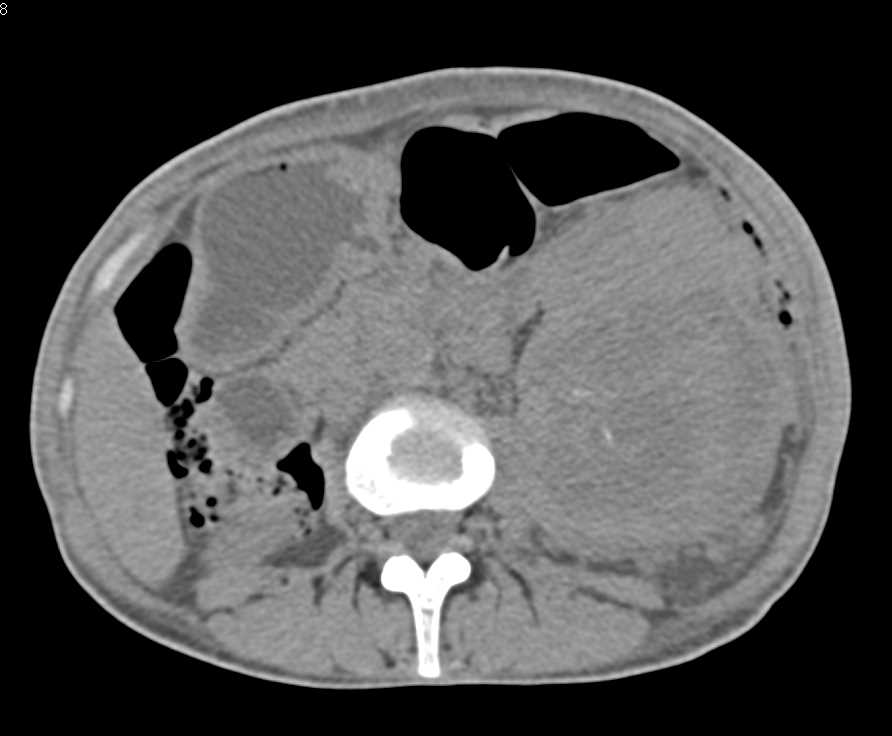

Left Hydronephrosis